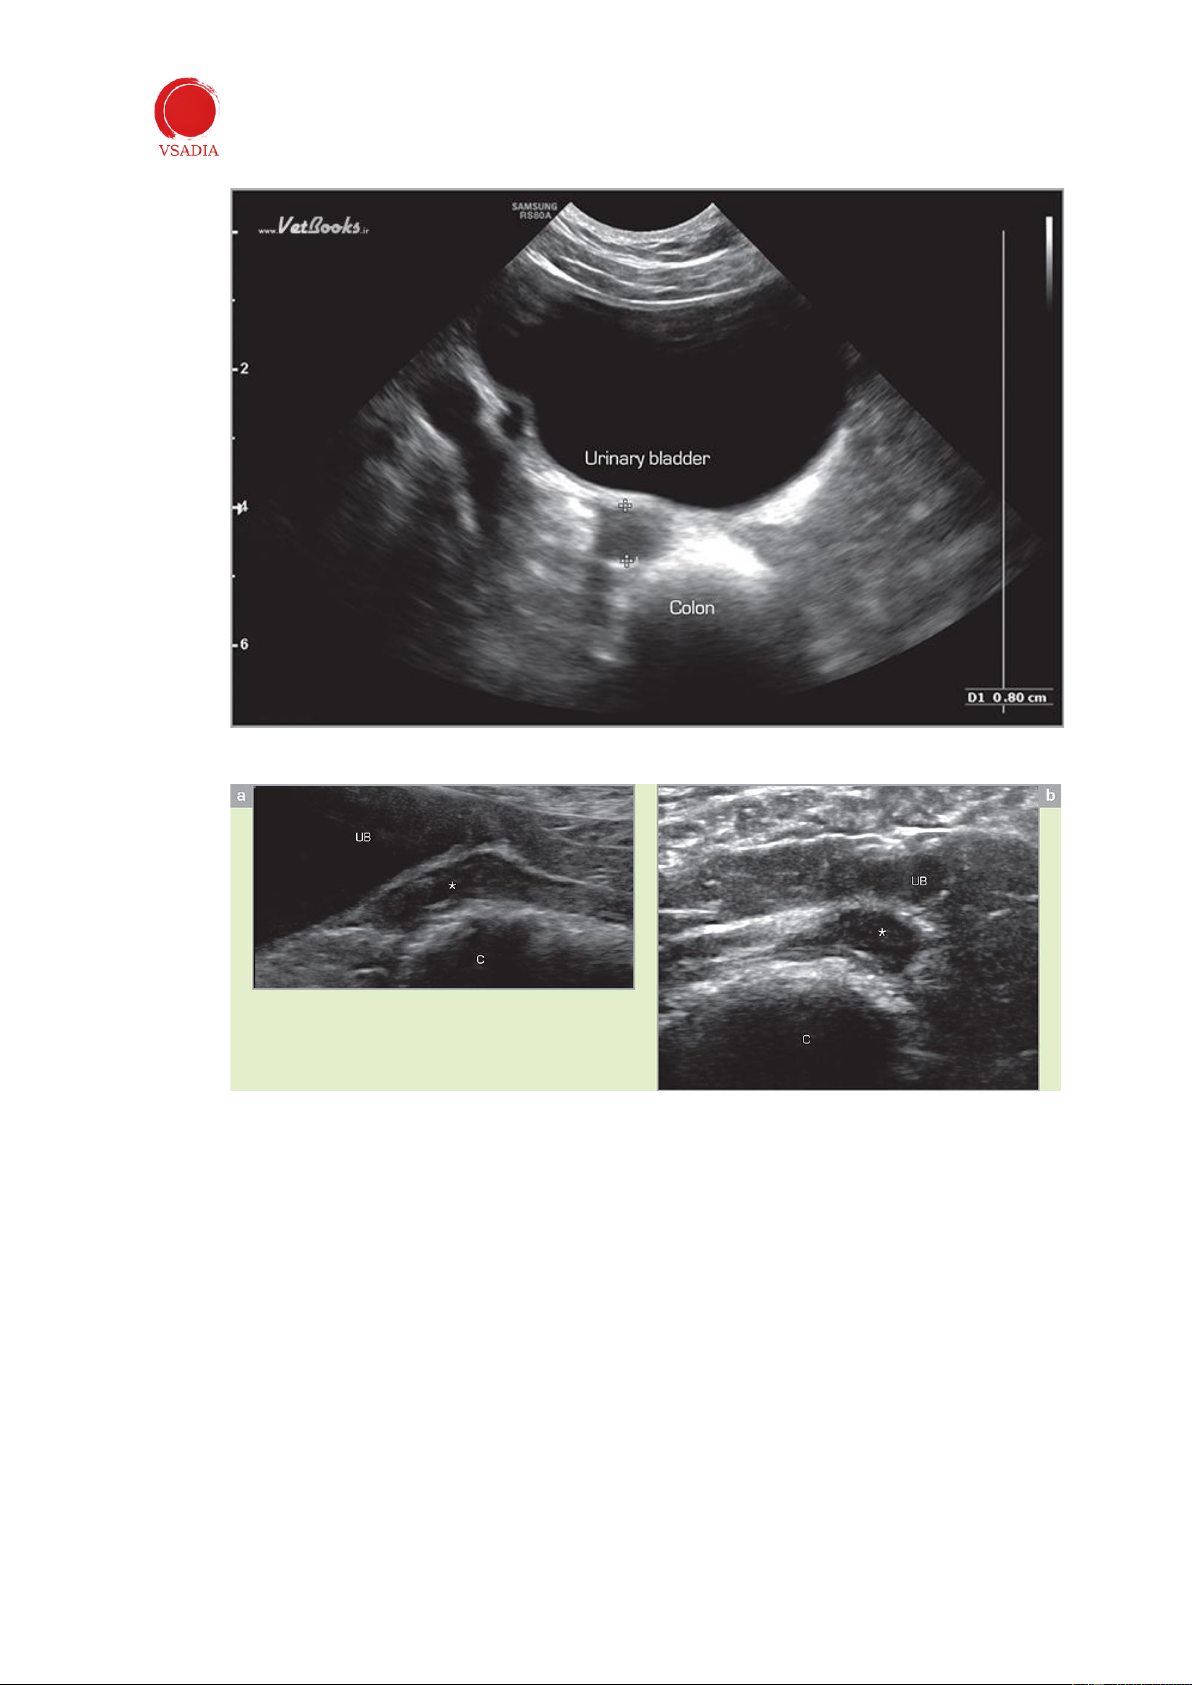

Xác định bàng quang và đại tràng rồi trượt đầu dò về phía sau (Hình 4). Tử cung (hoặc

gốc tử cung nếu con cái đã triệt sản) nằm giữa bàng quang và kết tràng (Hình 5 và 6).

Hình 4: Sau khi xác định bàng quang và kết tràng, đầu dò được di chuyển về phía sau để xác định tử cung hoặc

gốc tử cung nằm giữa bàng quang và kết tràng.

Hình 5: Hình ảnh cắt ngang của tử cung . Thân tử cung giảm âm được nhìn thấy giữa bàng quang và đại tràng.

Hình 6: Hình ảnh dọc (a) và ngang (b) của cuống tử cung (*) ở chó lai đã được triệt sản. Gốc tử cung được nhìn

thấy ở phía sau bàng quang. UB: bàng quang tiết niệu; C: đại tràng. -